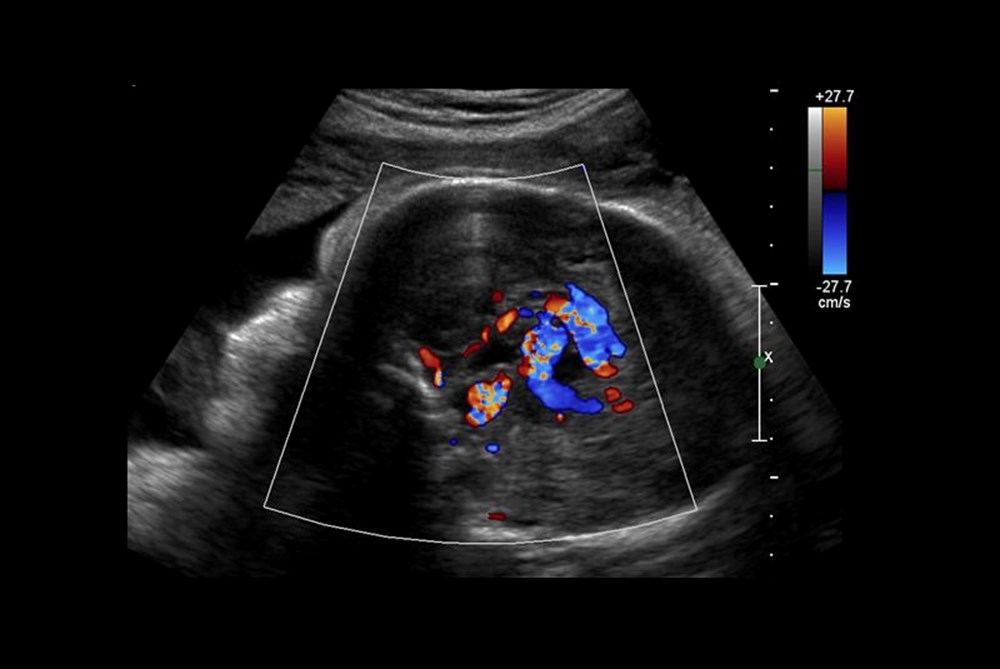

ABD'li doktorlar, türünün ilk örneği olan bir beyin ameliyatını çocuk henüz anne karnındayken gerçekleştirerek, doğmamış bir bebeği kesin ölümden kurtardı. Genetik bir bozukluk olan Galen damarı Malformasyonu'ndan (VOGM) muzdarip rahimdeki bebeğin kafatasını kesmeyi ve ardından gelişmekte olan beyni ameliyat etmeyi içeren titiz bir prosedür gerçekleştiren doktorlar, dünyada ilk kez yapılan operasyon ile birçok çocuğun hayatının kurtarılabileceğini müjdeledi.Türünün ilk örneği olan ve hayat kurtaran bir prosedürle anne karnındaki bir bebeğe beyin ameliyatı yapıldı.ABD'li doktorlar doğmamış çocuktaki ölümcül bir damar rahatsızlığını tedavi ederek doğumdan kısa bir süre sonra kalp yetmezliği ve felç geçirmesini önledi. Daha önce de rahimde beyin ameliyatı yapılmıştı, ancak Galen Damarı Malformasyonu (VOGM) adı verilen bu nadir hastalık için yapılmamıştı.Anneyi 34. haftada ameliyat eden bilim insanları, operasyonu yönlendirmek için ultrason kullandı. BEBEK SAĞLIKLI BİR ŞEKİLDE EVİNE DÖNDÜBoston Çocuk Hastanesi'nden Dr. Darren Orbach konuyla ilgili yaptığı açıklamada, "Genellikle doğumdan sonra görülen bebeğin sağlığındaki düşüşün ortaya çıkmadığını görmek bizi çok heyecanlandırdı. Şu anda altı haftalık olan bebeğin, ilaç kullanmadan, normal beslenerek ve kilo alarak eve döndüğünü bildirmekten memnuniyet duyuyoruz. Operasyonun beyin üzerinde herhangi bir olumsuz etki belirtisi yok." dedi. GALEN DAMAR FORMASYONU HAKKINDABununla birlikte, Galen Damar Malformasyonu (VOGM) her yıl yüzlerce bebeği etkiliyor ve çocuklar doğumun ilk birkaç gününden sonra hayatta kalamayabiliyor. Hastalık, beyindeki atardamarların kanı kılcal damarlar yerine doğrudan toplardamarlara akıtmasına neden olarak kalbin boğulmasına ve beyin hasarına yol açıyor.Mevcut tedaviler ise şimdiye kadar bebeğin doğumundan sonrası ile sınırlıydı, ancak bu noktada çoğu vakada beyin hasarı çoktan meydana gelmiş oluyordu. "Stroke" adlı bilimsel dergide sonuçları açıklanan yeni cerrahi operasyon, hastalığı bebeği etkilemeden önce iyileştirmeyi amaçlıyor.Diğer taraftan, operasyon kapsamında 10 sağlık görevlisinden oluşan bir ekip, annenin karnından uzun bir iğneyi bebeğin beyninin arterlerin etkilendiği kısmına yönlendirmek için ultrason kullandı. Doktorlar, daha sonra damarlara geri akışı engellemek için damar içine küçük bir madde enjekte etti.Dr. Orbach, "Bu yaklaşım, Galen Damarı Malformasyonu’nun tedavisinde büyük bir potansiyele sahip. Malformasyonu doğumdan önce onarıyoruz ve doğumdan sonra tersine çevirmeye çalışmak yerine kalp yetmezliğini ortaya çıkmadan önlüyoruz. Bu, bu bebekler arasında uzun vadeli beyin hasarı, sakatlık veya ölüm riskini önemli ölçüde azaltabilir." diye konuştu.